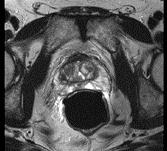

问题 男性,66岁,排尿困难多年,现感会阴部疼痛3个多月,指肛检查触及前列腺表面不规则,行MRI检查,如图所示,你认为最可能的诊断是 ( )

选项 A、前列腺钙化 B、前列腺出血 C、正常前列腺 D、前列腺癌 E、前列腺增生

答案 D